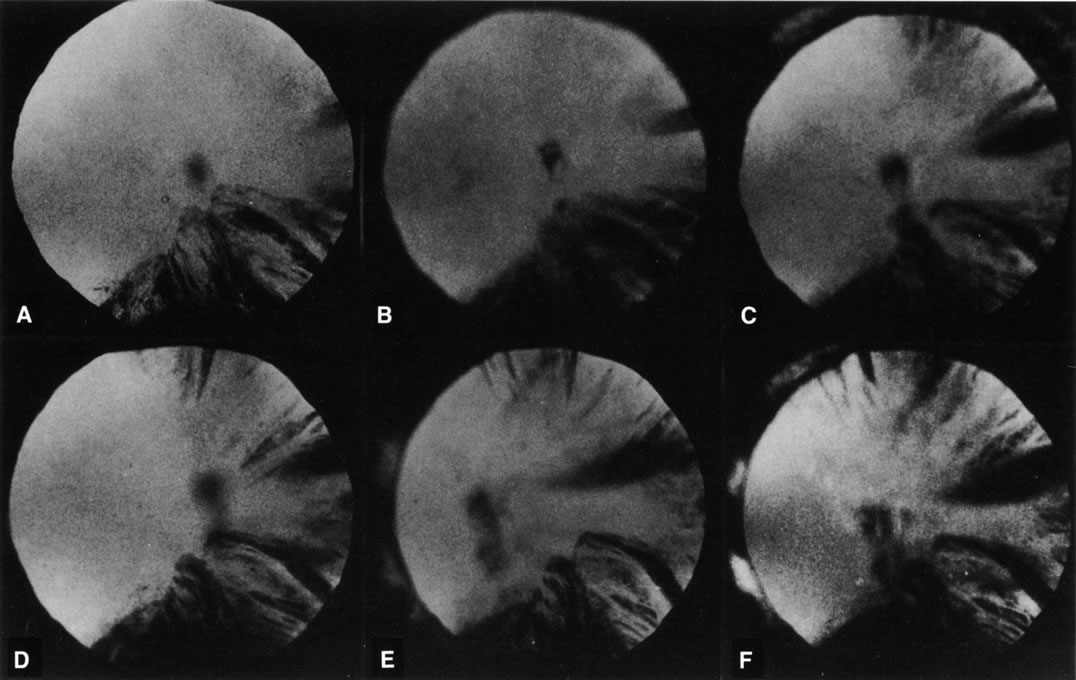

Retroillumination uses the light reflected from the fundus to highlight opacities. This is very useful in examining cortical and posterior subcapsular cataracts (Figs. 1, 3, 7, and 8). However, some cortical water clefts and early posterior subcapsular opacities may not be easily seen with retroillumination if they are not dense enough to cast shadows or only refract the retroilluminate light; these can be best seen with the broad beam. Using retroillumination on nuclear cataracts does not give much information because these usually do not cast shadows. However, as seen in Figure 2B, a change in the refractive index can be seen toward the center. Usually, the outline of the nuclear cataract can be seen as a result of a “magnifying lens” artifact. This is also easily observed during direct and indirect ophthalmoscopy. Several retroillumination cameras (modified slit lamps with the slit beam fixed for retroillumination and depolarizers built in to remove corneal reflex from the image) have been developed and are being used for documenting cortical and posterior subcapsular cataracts.49, 50

Fig. 8. Follow-up retroillumination photographs of an eye with a cortical cataract, obtained at various intervals. A. First visit (1-21-87); B. 1 year later (1-27-88); C. 22 months later (11-14-88); D. 28 months later (12-4-89); E. 35 months later; F. 41 months later (6-18-90). With such photographs one may be able to plot the progression rate of a cortical cataract, and aid in performing longitudinal studies. Note the central opacity, which is out of focus and represents a small posterior subcapsular cataract.